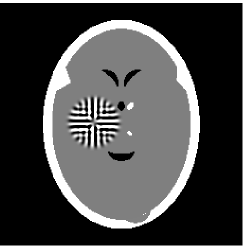

Furthermore, we used the classic ART iteration as the iteration operator in our numerical experiments. In order to compare the proposed superiorization algorithm with the classic superiorization algorithm, we applied the classic superiorization and -PP superiorization algorithm to two phantoms (see figure 1). The first one is the Shepp-Logan phantom[30], and the second one is the head phantom with a ghost which is invisible at 22 specified projection directions [10, 31]. In addition, we compare the performances of the two algorithms for the noiseless and noised data with different projections. In all experiments, the noised projection data was corrupted by additive Gaussian white noise with variance . We record the iterations, running time of program and mean square error (MSE) of different algorithms, where MSE is computed by

The reconstruction images from the noiseless projection data were shown in the Fig. 2. From Fig. 2, we can observe that the classic and the proposed algorithms can reconstruct images from the three projection data. In order to show the advantages of the proposed algorithm visually, the central vertical line of the differences between the reconstructed images and the original image are present in Fig. 3. We can observe that the -PP superiorization is more efficient than the classic superiorization in the aspect of suppressing the artifacts in the reconstructed images.